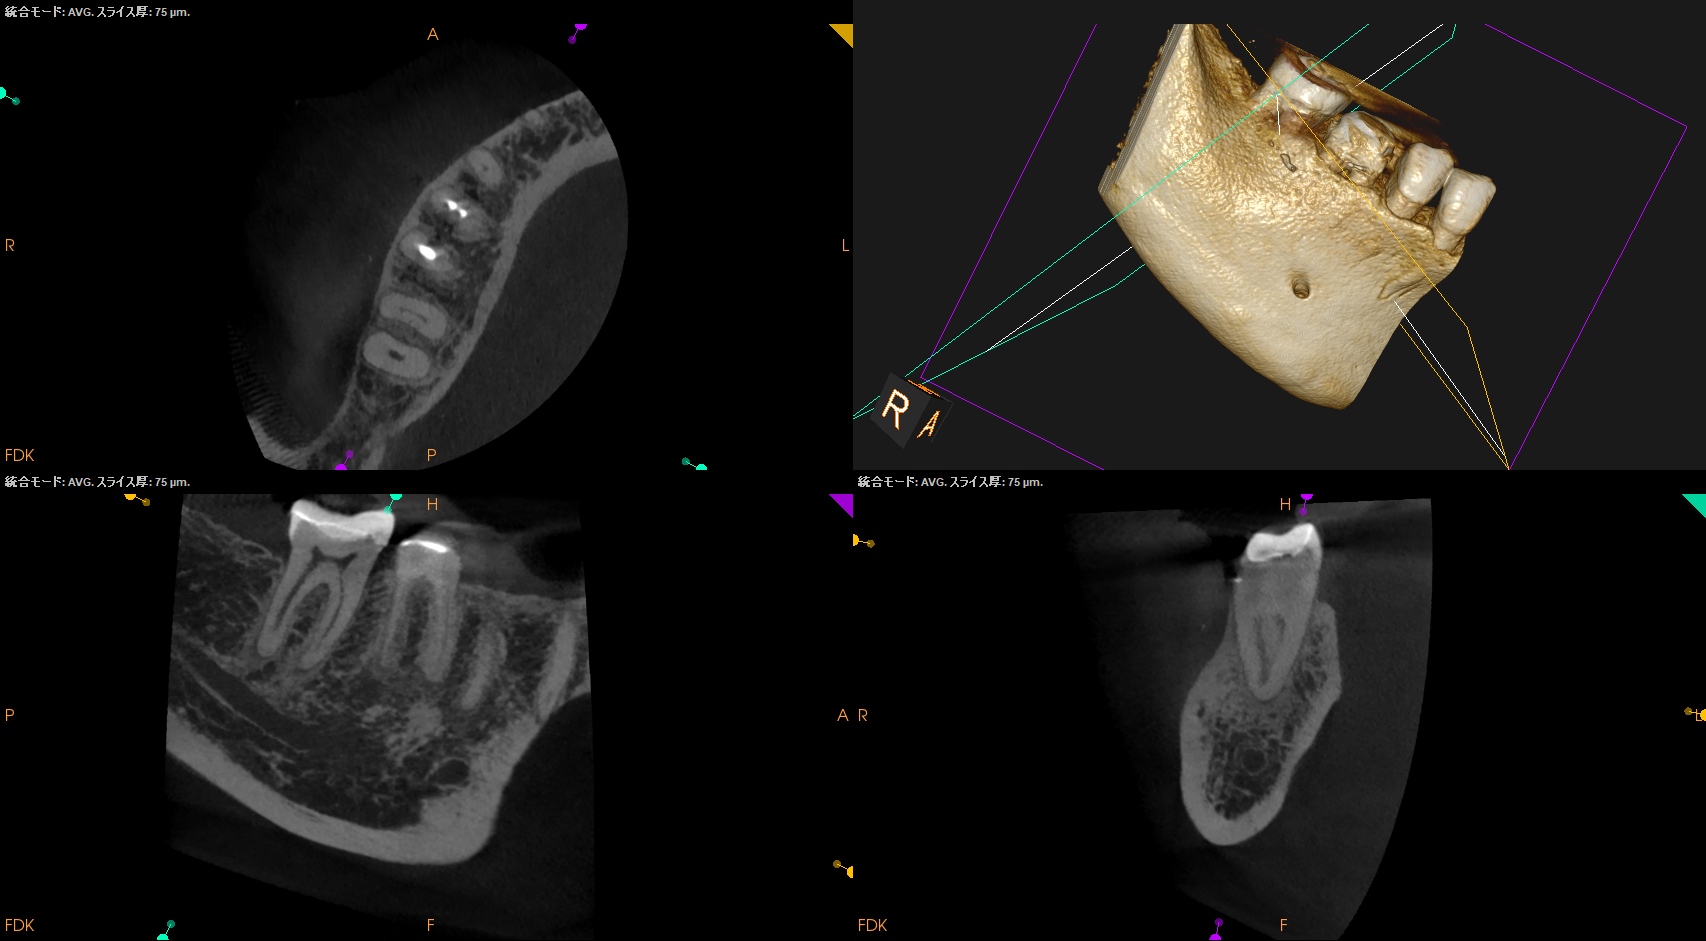

CBCT(2025.8.29)

#30

MB

ML

D

#31

MBとML,どちらがストレートか?と言えばMLの方だろう。

MLをメイン根管にしてMBはそこに合流するという風に形成・根充すべきだろう。